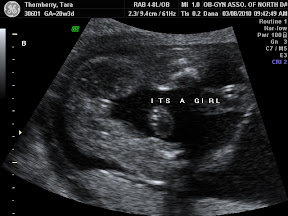

Today was the 'big scan'. It was so amazing. Seeing not only the girl's hearts beat, but seeing the four chambers of each of their hearts beating beautifully. The technician measured around their little noggins and their tummies. She measured the length of their legs and arms. We got to see their adorable little feet as well as their kidneys and stomachs. The technician even surprised us with a 4d picture of each of them. They're just beautiful. They've apparently already started sucking on their thumbs and playing footsie with one another. Baby A was especially active starting out head down, kicking her sister in the head, and then flipping over so that they were both feet down.

Baby A had a heart beat of 148 and was 14 oz and baby B had a heart beat of 152 and was 13 oz. Needless to say they are two very healthy girls.

Here are some of the pictures from today's visit:

Baby A 'girl':

Baby B 'girl':